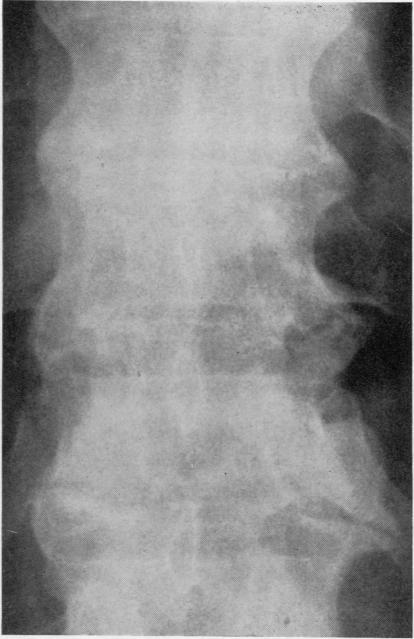

Radiological changes in the sacro-iliac joints and spine of patients with psoriatic arthritis and psoriasis.

Ann Rheum Dis. 1968 Jan;27(1):1-6. doi: 10.1136/ard.27.1.1.